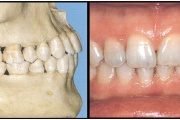

kahepoolse lõhega lapse hambumus

Valehambumus

Hammaste asendianomaaliad on tingitud tavaliselt arenguhäirest.